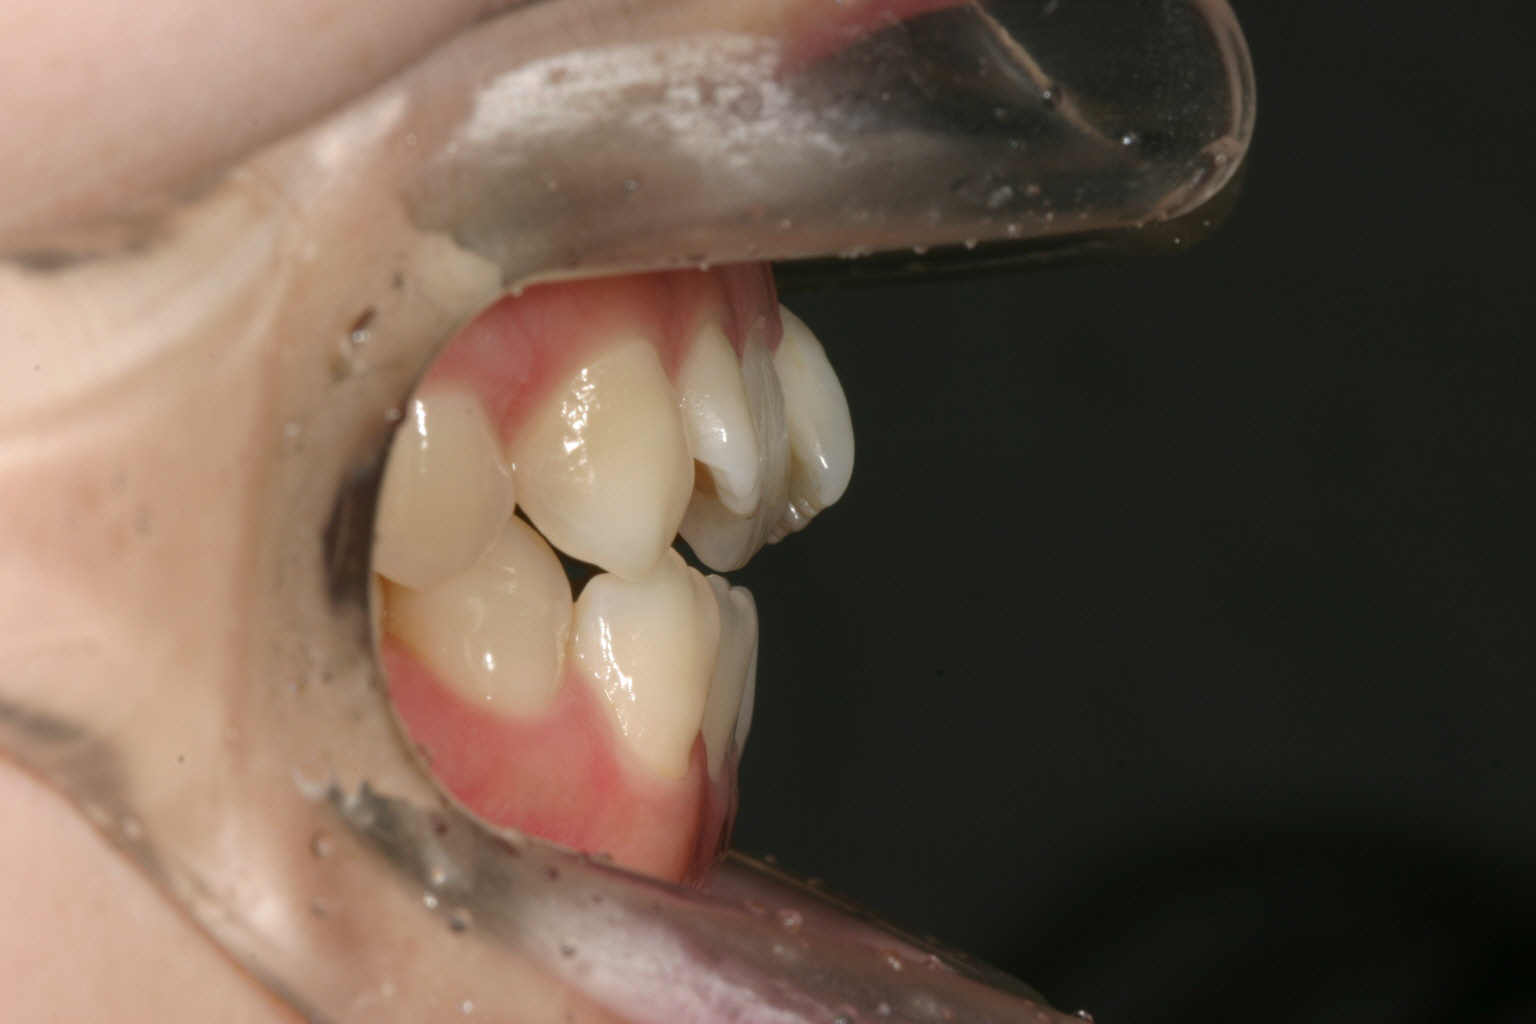

側面観も叢生の為出っ張ってます。

前歯部の開咬も殆どふさがってきています。 正中もピッタリです。 少し受け口傾向の為エラスティックを利用しました。 その為下顎前歯の犬歯のところに下向きの角が見受けられます。

開咬も改善し最高のオーバージェットです。